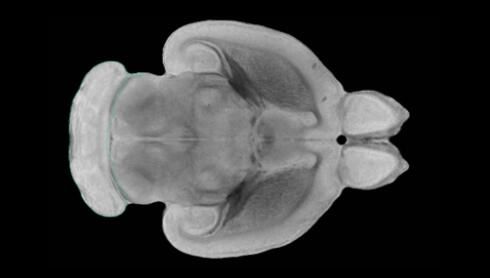

隨著機體年齡增加,肌肉和關(guān)節(jié)都會變得僵硬,這就會使得日?;顒幼兊酶永щy,本文研究表明,我們的大腦也是如此,與年齡相關(guān)的大腦僵硬對大腦干細胞的功能或許有著重要影響。文章中,研究人員對年輕和老化大鼠的大腦進行研究闡明了年齡相關(guān)大腦僵硬對少突膠質(zhì)前體細胞(OPCs,oligodendrocyte progenitor cells)功能的影響。OPCs是一類對維持正常大腦功能非常重要的大腦干細胞,其對于髓磷脂的再生也非常重要,髓磷脂是神經(jīng)組織周圍的脂肪鞘,在多發(fā)性硬化癥中髓磷脂的再生常常會被損傷,機體老化對這些細胞的影響常常會誘發(fā)多發(fā)性硬化癥的發(fā)生,這些細胞的功能在老化的健康人群中同樣會下降。

為了確定老化OPCs的功能缺失是否可以被逆轉(zhuǎn),研究人員將來自老化大鼠機體的老化OPCs轉(zhuǎn)移到了年輕大鼠柔軟的海綿狀大腦組織中去,值得注意的是,這些老化的大腦細胞能夠重新恢復(fù)活力,其行為非常像年輕更加強壯的細胞。這項研究中,研究人員在實驗室中開發(fā)出了具有可變僵硬程度的新型材料,并在受控環(huán)境下研究這些材料的生長及其對大鼠大腦干細胞的影響,這些材料能被工程化改造具有和年齡或老化大腦相似的柔軟程度。